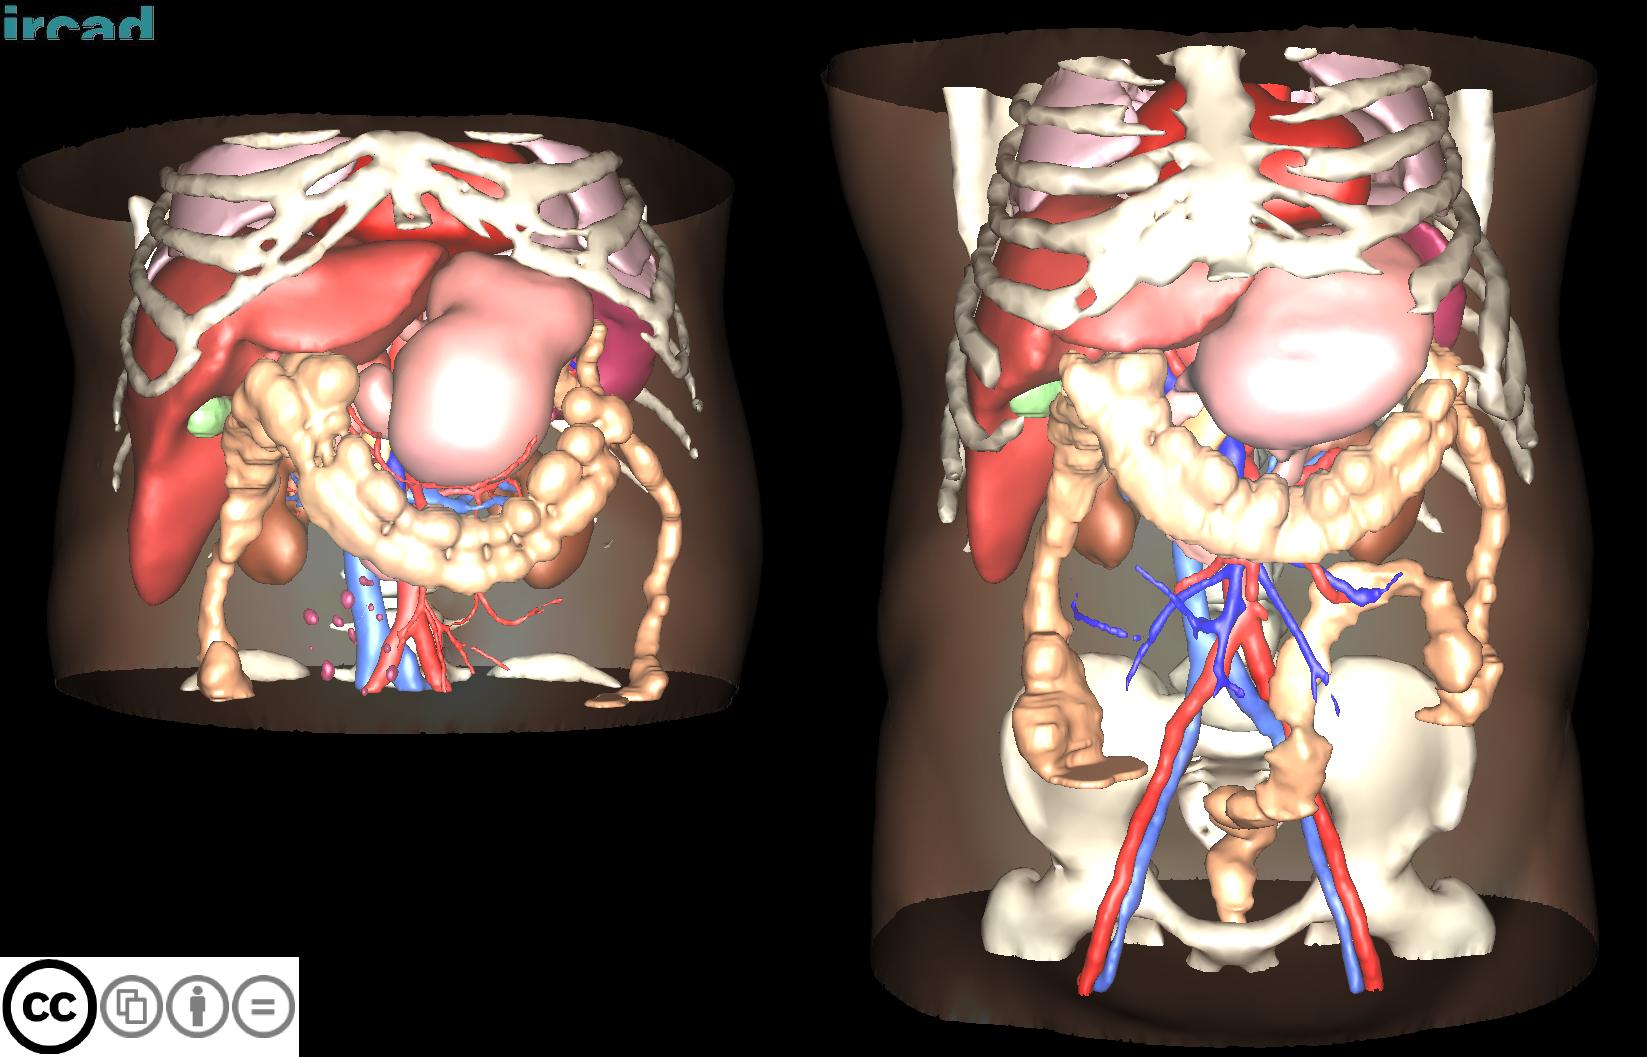

3D-IRCADB

| 3D-IRCADb 01 02 | 肝脏/肝肿瘤 | 分割 | CT | 20+2 | surface mesh | dcm |

| 3D-IRCADb是比较早的一个数据集,有两个子集,分别包含20组和2组CT片子。 |

3D-IRCADb是比较早的一个数据集,有两个子集,分别包含20组和2组CT片子。